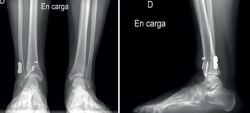

Figura 6. Radiografía de control en carga con proyecciones anteroposterior y lateral realizada tras la segunda intervención en la que se aprecia la colocación de 2 dispositivos sindesmales y de tornillo para fijar el fragmento de Tillaux-Chaput, además de una adecuada congruencia articular y buen eje del miembro.